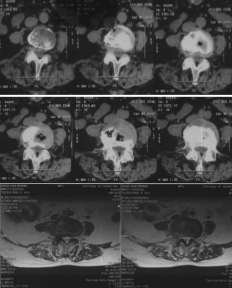

腰椎CT、核磁可见腰4-5椎管狭窄

椎间孔镜下可见神经根受压解除